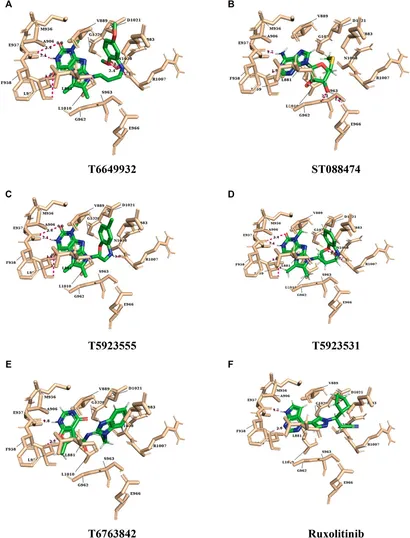

GeneLink。A Dual-Selective Channel Attention Network for Osteoporosis。fphar-13-837369-g004.jpg。R6年秋田県産ひとめぼれ梱包込み10キロ。減農薬米。Franklin Brass Solid Bar (10-Pack) Cabinet Handles 3' Hole。即購入可能袋の上から触るスクイーズ!シリコン製のとても柔らかいスクイーズです袋の上から触って楽しむタイプです♡日本の店頭ではほぼ販売されないタイプかと思います・いちごタルト2980・ハートチョコパン1980・ミニシャム猫2980・ランダムミニスクイーズ1980(おまけ)4点セットハンドメイドのスクイーズ販売で購入した商品です袋から出すとペタペタしています画像と実物では若干色味が異なる場合がございますので予めご了承ください 韓国 中国 スクイーズ シリコン製スクイーズ 海外スクイーズ ハンドメイド 手作り ストレス発散 癒し アイテム食品用シリコン もちもち ぷるぷる SNS TikTok 動物 キャラクター おもちゃ 子ども 大人 プレゼント fumifumiスクイーズ